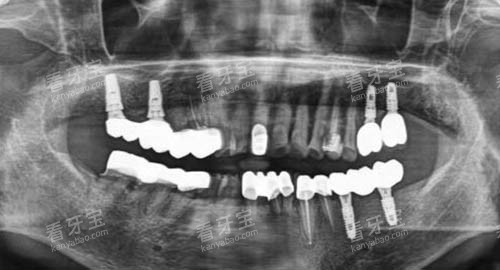

从硬件设施来看,诺言口腔引进了新型的口腔诊疗设备,如智能化口腔全景机、口腔CT等。

这些设备不仅能够为医生提供比较准的诊断依据,还能大大提高诊疗结果。

新型的设备与可靠的医生团队相结合,使得威海诺言口腔在口腔疾病的诊断和治疗方面达到了较高的水平。